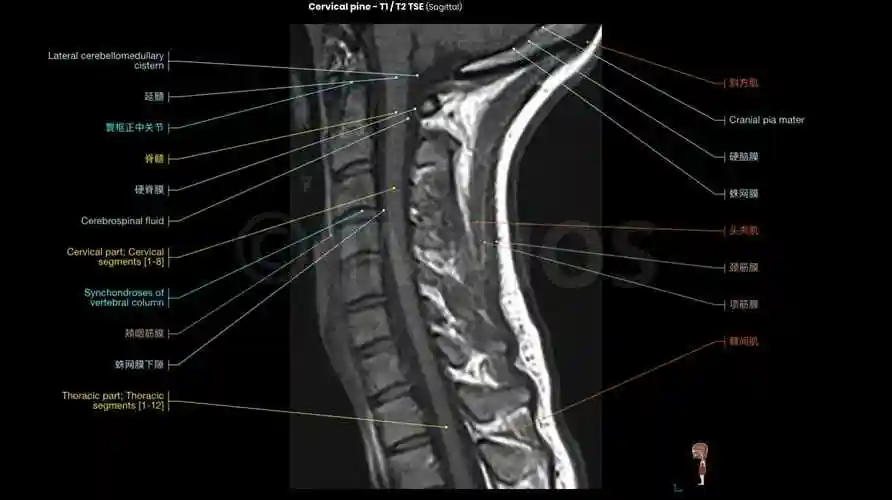

颈椎间盘突出征核磁共振矢状位(mri)

颈椎mri解剖图(轴向,冠状,矢状切片)

脊柱mri解剖图片

颈椎病的mri诊断技巧